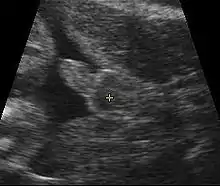

Obstetric ultrasonography, either transvaginally or transabdominally, checks for various markers of fetal sex. It can be performed at or after week 12 of pregnancy. At this point, 3⁄4 of fetal sexes can be correctly determined, according to a 2001 study.[50] Accuracy for males is approximately 50% and for females almost 100%. When performed after week 13 of pregnancy, ultrasonography gives an accurate result in almost 100% of cases.[50]